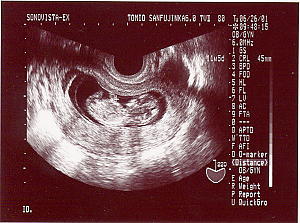

< 5週目以降のエコー >

+と+で挟まれてるのが赤ちゃんです。左隅にあるのが頭からお尻までの大きさです。

5週目の妊娠発覚時のエコー まだまだちっちゃくて何がなんだか・・・ 5.4ミリです。 |